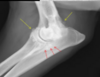

identify

elbow dysplasia yellow arrows: osteophytes